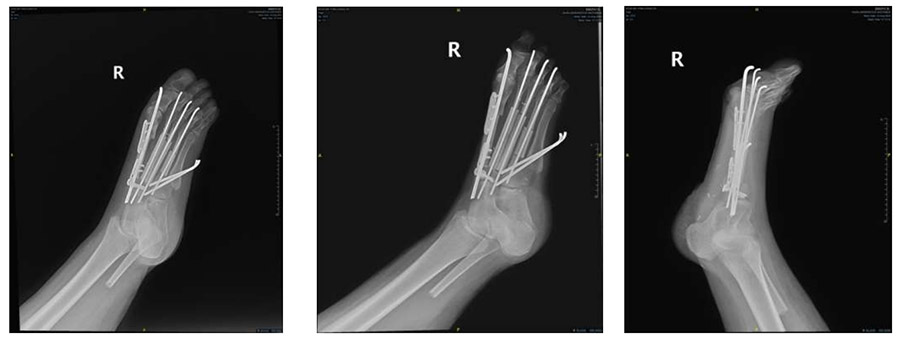

Ameliyat Esnası: Eski insizyon hattını eksize edecek şekilde planlama yapılması ve tümör çıkarıldıktan sonra oluşan boşluğun fibula grefti ile rekonstrüksiyon yapılması görülmekte

Ameliyat Esnası: Tümör çıkarıldıktan sonra oluşan boşluğun fibula greftleri ile rekonstrüksiyonu görülmekte